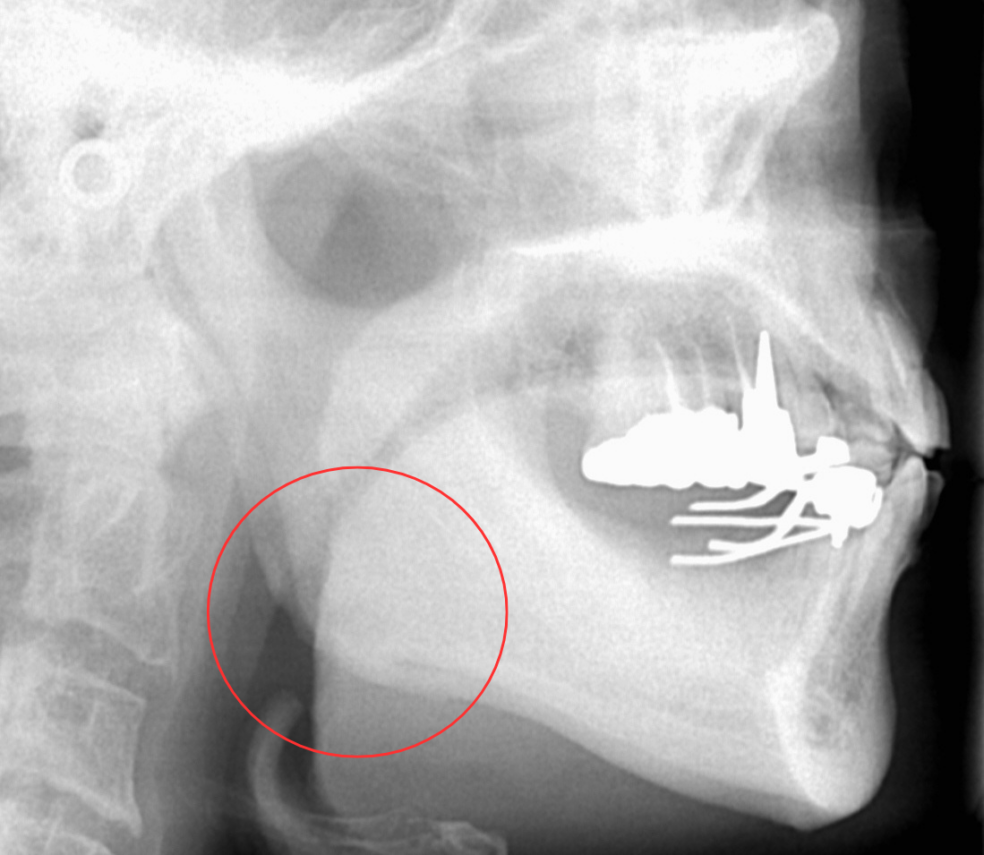

そもそも、噛む力が強いとはどういうことでしょう。下顎が非常に発達している方の写真です。下顎角(〇で囲まれた部分)は発達しています。

この部分は咬筋(こうきん)という、お口を閉じるときに主に働く筋肉が垂直的に走行しています。筋が収縮すると、そのまま力となって、歯や、歯を喪失した場合は粘膜に加わることになります。